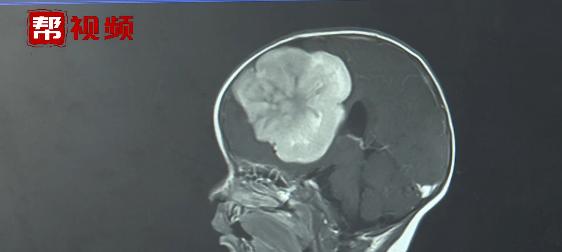

家屬趕忙將孩子送往了福建省福州兒童醫(yī)院救治。醫(yī)生檢查發(fā)現(xiàn),女嬰的頭圍比正常孩子稍大,考慮兒童中風(fēng)偏癱的可能低,醫(yī)生傾向孩子可能是顱內(nèi)長了腫瘤。通過CT、核磁共振檢查,醫(yī)生果然在孩子的大腦前部發(fā)現(xiàn)了一個小蘋果大小的巨大腫瘤。

琳琳顱內(nèi)的腫瘤已經(jīng)擠占了將近三分之一的大腦,破壞了腦脊液的正常循環(huán),導(dǎo)致出現(xiàn)腦積水。